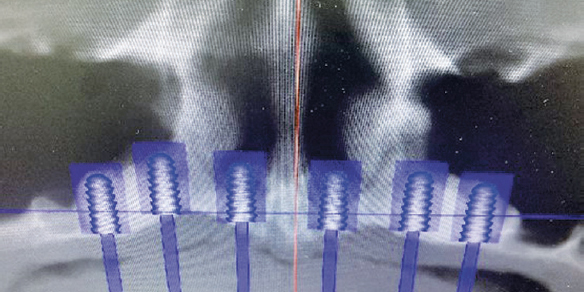

Через полгода после синус- и назалифтинга пациентке проведено планирование (рис. 4) и установка дентальных имплантатов (рис. 5).

Рис. 4. Планирование имплантационного лечения на верхней челюсти

Fig. 4. Planning of the implantation treatment on the upper jaw

Рис. 5. Компьютерная томограмма верхней челюсти с установленными дентальными имплантатами

Fig. 5. Computed tomography of the upper jaw with dental implants